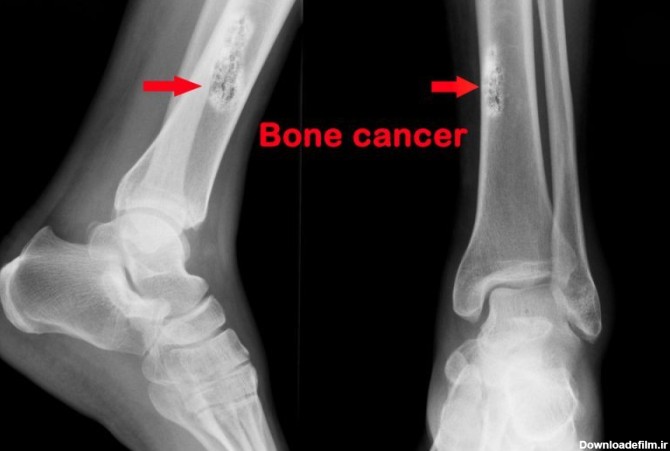

سرطان استخوان پا از جمله بیماریهای نادر و سختی است که عموما خوشخیم است و خوشبختانه با تشخیص بهموقع قابل درمان است.